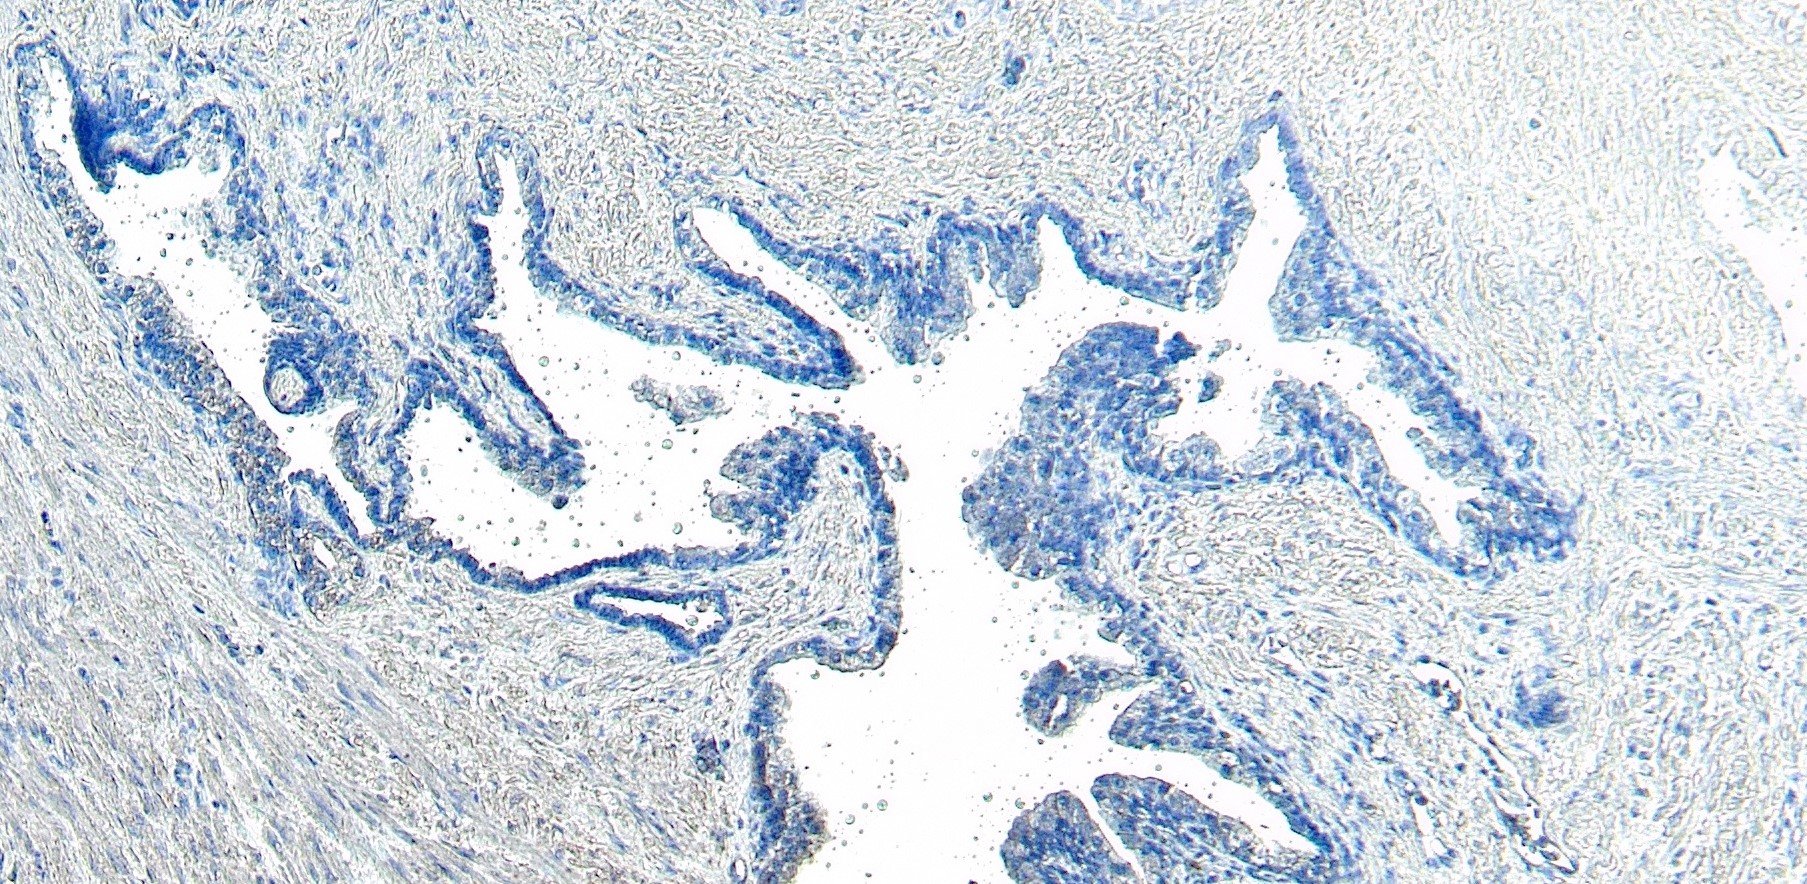

ApplicationsImmunoFluorescence, ELISA, ImmunoHistoChemistry

- ApplicationsImmunoFluorescence, ELISA, ImmunoHistoChemistry